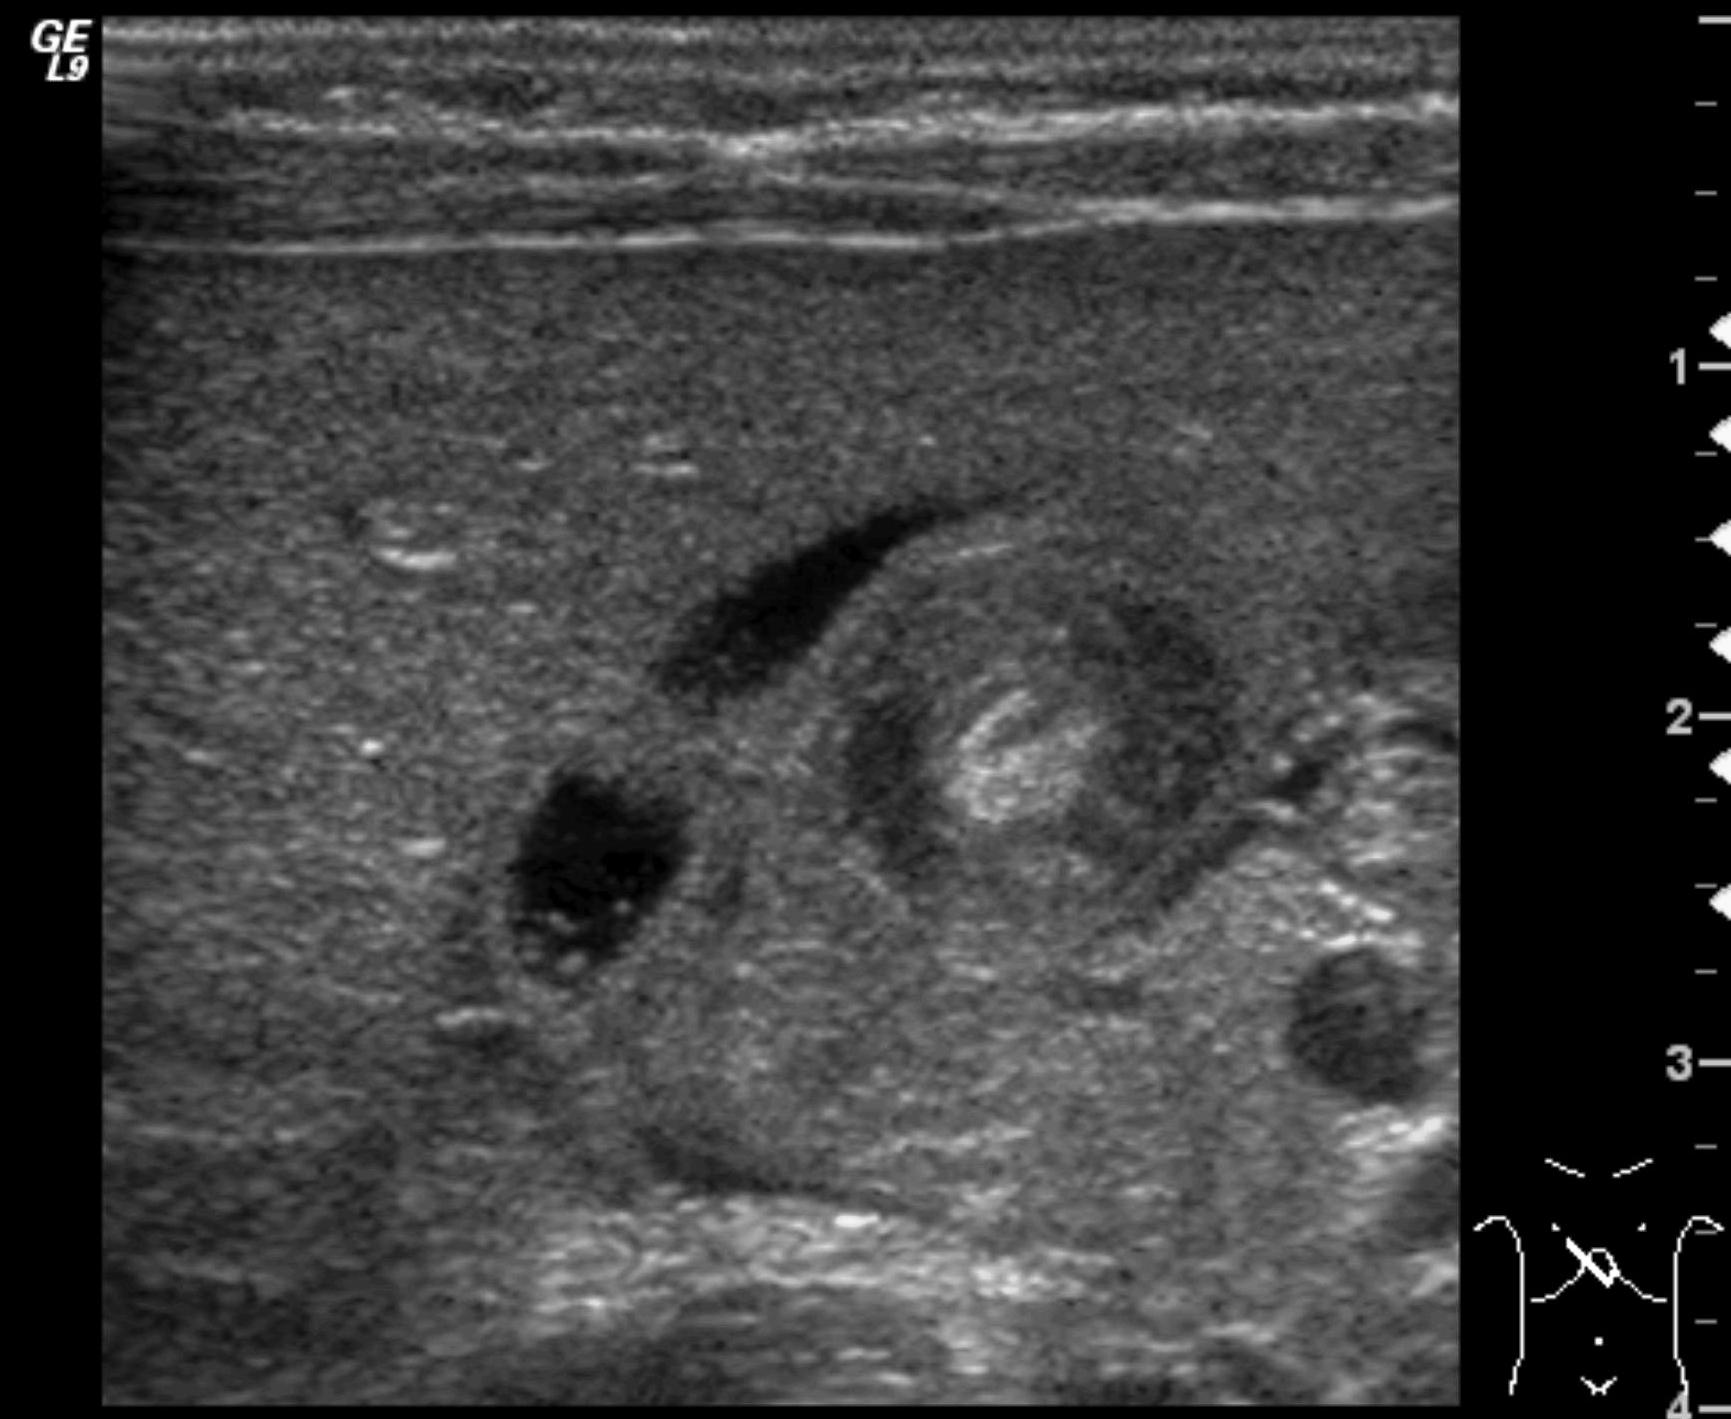

Invagination. A distal intestinal loop invaginating to a proximal intestinal loop can result in a mechanical intestinal obstruction, and cause ischemic damage. It most frequently occurs in infants (3-24 months) with recurring, colic-like complaints, distended intestines, a palpable mass and with frequent vomiting and bloody stool. Invagination requires immediate diagnosis and desinvagination. US exam reveals the invaginated intestines as a “target” sign in axial cross section and looks like a “pseudokidney” in longitudinal cross section. The therapy is hydrostatic or pneumatic desinvagination. Perforation and/or peritonitis are absolute contraindications to these procedures. Hydrostatic desinvagination can be performed under fluoroscopy or with US guidance and is considered successful if air or the contrast material appears in the terminal ileum and the invaginated loop disappears. If these efforts do not succeed, surgical desinvagination is needed.

Image

17. “Target” sign. Invagination. .